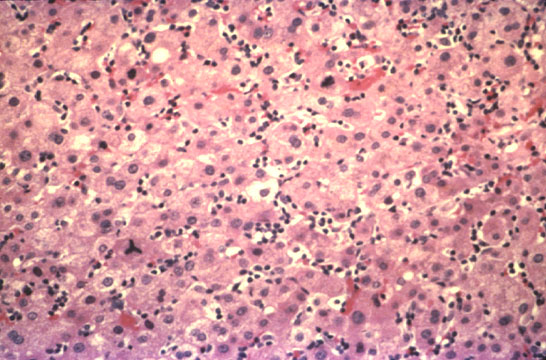

Mononucleosis hepatitis is characterized by peculiar necroinflammatory changes which, at the difference of classical viral hepatitides consist of more inflammation and less necrosis. There is marked mononuclear cell infiltration of sinusoids and portal fields contrasting with mild hepatocellular necrosis. The sinusoids are filled and distended with mononuclear cells which are large and sometimes clustered to resemble granulomas sometimes similar to sarcoidosis. The sinusoids are swollen adn the liver cell plates, in some areas, may be compressed and atrophic. Occasional Councilman bodies may be seen. Obviously, the sinusoidal infiltration reflects the mononucleosis picture of the peripheral blood.

Another peculiar feature is the presence of a marked regenerative activity of hepatocytes with presence of increased number of binucleate cells, polyploid nuclei and mitotic figures. This is probably the liver disease with the highest number of mitoses. Portal tracts are healvily infiltrated by mononuclear inflammatory cells but there is mild erosion of the limiting plates.

Fig. 133 - Infectious mononucleosis hepatitis

Marked mononuclear cell infiltration of the sinusoids without significant necrosis. H&E stain.

Fig. 134 - Infectious mononucleosis heapatitis

High power of previous illustration showing the signs of high regenerative activity: binucleate cells and a mitotic figure. H&E stain.